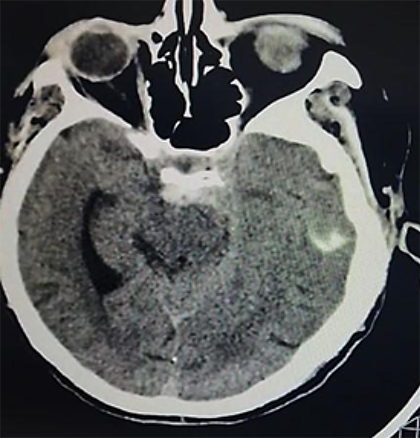

Paciente femenino de 52 años, proveniente y residente de Cochabamba, provincia Quillacollo, acude al servicio de emergencia del Hospital Obrero Nro. 2 de la Caja Nacional de Salud; con antecedentes de diabetes mellitus tipo 2, hipertensión arterial, enfermedad renal crónica, estadio 5 en hemodiálisis y un accidente cerebrovascular hemorrágico hace 1 año; es medicado con metformina 850 mg, carvedilol 12,5 mg, losartan 100 mg, alfa metildopa 500 mg y recibe hemodiálisis desde hace 1 año, trisemanal; presenta un cuadro clínico de 8 horas de evolución caracterizado por cefalea holocraneana, pulsátil, súbito, de intensidad moderada, acompañado de somnolencia, entumecimiento a nivel de columna cervical-dorsal, paraparesia de extremidades inferiores y una escala de coma de Glasgow de 11-12/15. Ingresa por emergencia en mal estado general, con tendencia a la hipertensión PA: 231/174 mmHg, PAM: 183, FC: 96 latidos/min. Saturación de oxígeno 91% aire ambiente. Se solicitan algunos laboratorios: Glicemia 380 mg/dl, creatinina 6,9 mg/dl, sodio: 129 mEq/l (Tabla 1); rápidamente se solicita una tomografía axial computarizada de cráneo (TAC) simple (Figura 1a, b).